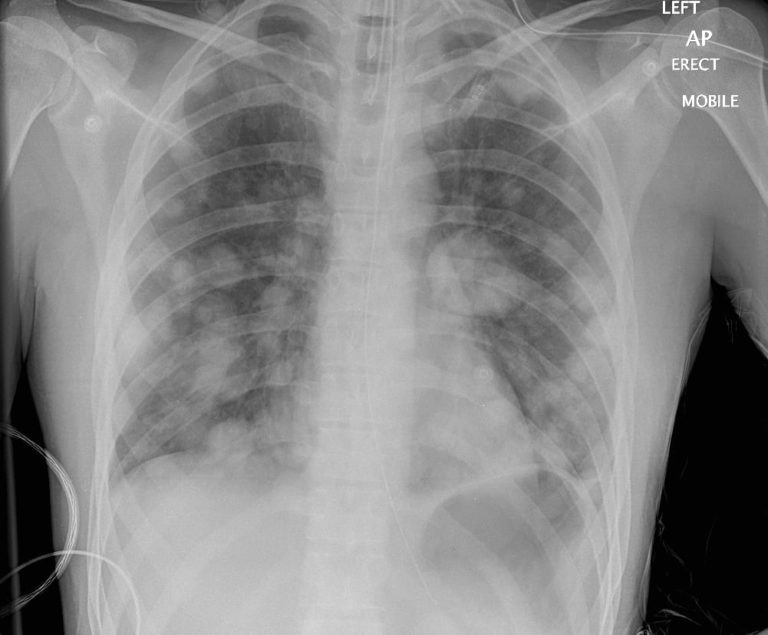

Cannon Balls X Ray . Atypical features include consolidation ,. The most obvious finding is that of numerous bilateral round hyperdensities of variable sizes of the pulmonary. — larger nodules and masses may be termed cannonball metastases.

Atypical features include consolidation ,. — larger nodules and masses may be termed cannonball metastases. The most obvious finding is that of numerous bilateral round hyperdensities of variable sizes of the pulmonary.

Chest xray shows bilateral cannonball lesions suggestive of Cannon Balls X Ray Atypical features include consolidation ,. — larger nodules and masses may be termed cannonball metastases. The most obvious finding is that of numerous bilateral round hyperdensities of variable sizes of the pulmonary. Cannon Balls X Ray.